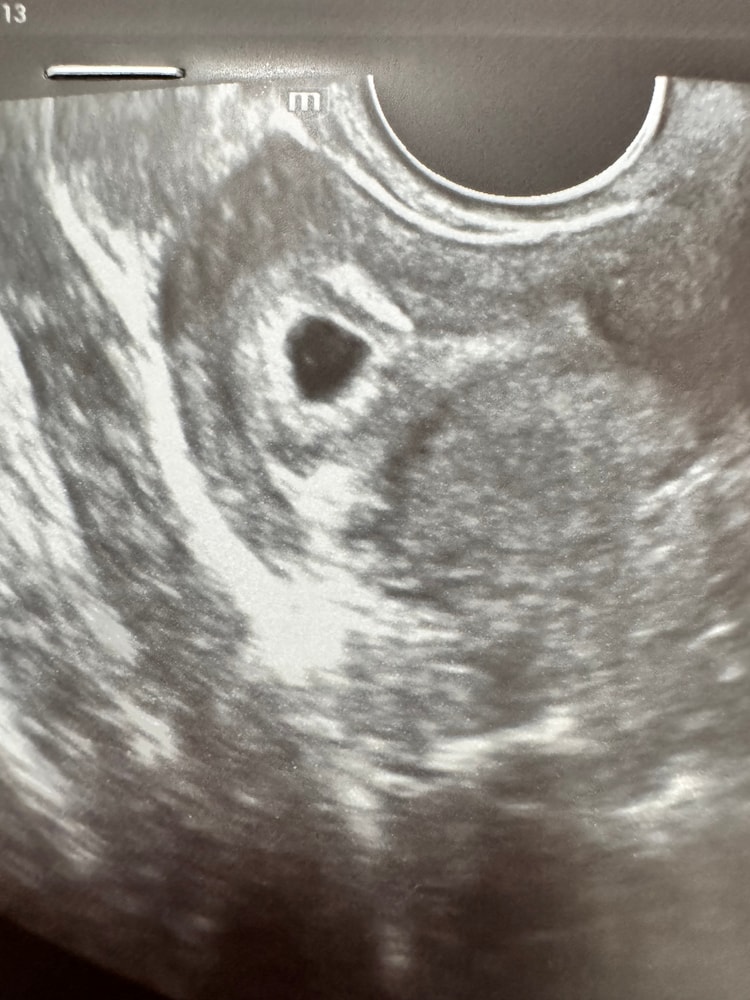

(: Кристина :), по месячным 5,4, а по узи поставили 5 неделек 😄

Я сегодня была на узи и поставили 5 нед, позднее оплодотворение предположили или замер. От зачатия так и получается. А по акушерским нед почти 9. Вот начала сдавать хгч в динамике, посмотрим.

Лёвушка, ой столько всего было😁 не даёт скучать)) лежим в больнице с угрозой пару дней, но всё хорошо. Сказали день другой ещё понаблюдают. Сегодня на узи 8+2 срок. Сердечко услышала впервые.

А так и ранее хгч падал и в одной клинике на узи не увидели ничего совсем и на чистку направили в больницу. А я пошла в другую и на след день увидели даже с сердечком.

Ростите большими 🥰 У меня по УЗИ тоже срок 8 недель и 1 день 😊